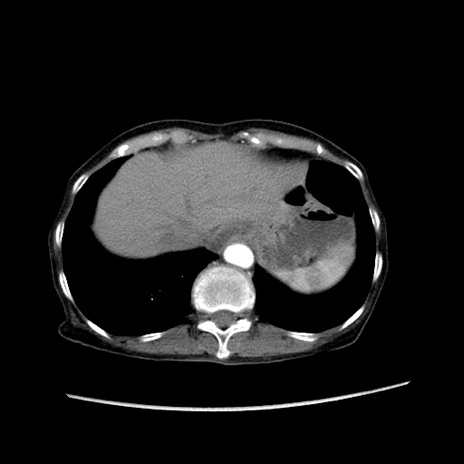

症例25(横断像)

【症例】80歳代女性

【主訴】胸のつかえ感

【現病歴】約9時間前に食後から胸のつかえた感じあり、嘔吐あり、来院。

【既往歴】胃癌(全摘)、胆摘、虫垂炎

【身体所見】心窩部に圧痛あり、反跳痛なし。

【データ】WBC 5700、CRP 0.05